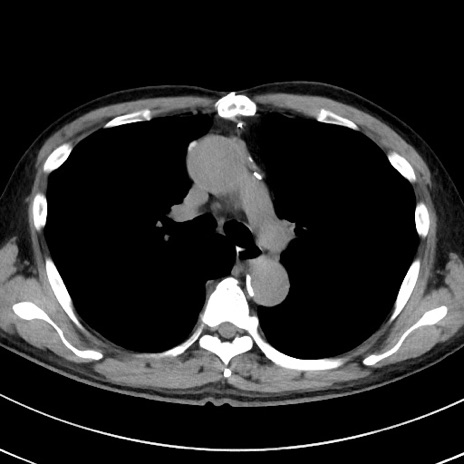

症例38(横断像)

【症例】70歳代 男性

【主訴】腹痛・嘔吐

【現病歴】昨晩より、嘔吐・腹痛あり。今朝になっても嘔吐あり。来院。

【既往歴】心臓バイパス手術、開腹胆摘、腸閉塞

【身体所見】BP 107/71mmHg、HR 116/min、腹部:平坦、軟、下腹部に軽度圧痛あり。反跳痛なし。

【データ】WBC 15100、CRP 0.32